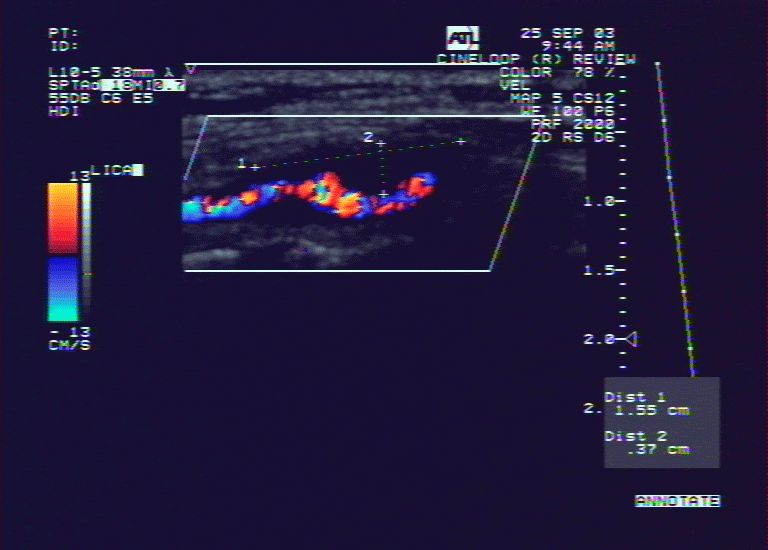

颈内动脉狭窄-超声波(图)